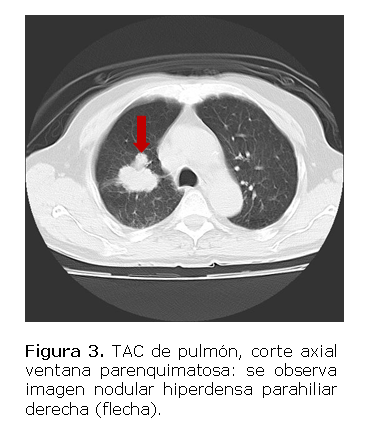

Tomografía de pulmón (Figuras 3 y Figura 4) se observa imagen hiperdensa de 67 UH que mide 45x46 mm en el hilio derecho a 57 mm de la carina sin afectar la luz del bronquiotronco derecho.